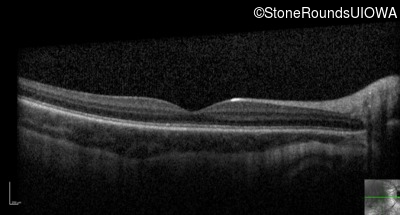

Optical Coherence Tomography - Right - 10/125

Exemplar

Optical Coherence Tomography - Left - 10/200

Exemplar / OCT Stack